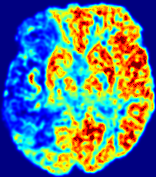

Figure 4: PIANO feature maps for another patient in the ISLES 2017 training set, where the lesion is located in the right hemisphere. Top row: segmented stroke lesion region (white) on different slices. The corresponding slices for the PIANO feature maps are shown in the following rows.

For a better insight into an estimated velocity field 𝐕𝐕{\bf{V}} and diffusion field 𝐃𝐃{\bf{D}}, we compute the following maps: (1) 𝐕rgbsubscript𝐕𝑟𝑔𝑏{\bf{V}}_{rgb}: Color-coded orientation map of 𝐕=(Vx,Vy,Vz)T𝐕superscriptsuperscript𝑉𝑥superscript𝑉𝑦superscript𝑉𝑧𝑇{\bf{V}}=(V^{x},V^{y},V^{z})^{T}, obtained by normalizing 𝐕𝐕{\bf{V}} to unit length and mapping its 3 components to red, green, blue respectively; (2) 𝐕2subscriptnorm𝐕2\|{\bf{V}}\|_{2}: 222 norm of 𝐕𝐕{\bf{V}}; (3) D𝐷D: scalar field in Eq. 5.

Fig. 3 and Fig. 4 show the PIANO feature maps estimated from two ISLES 2017 patients: all are highly consistent with the lesion in both cases. Details of the blood flow trajectories are revealed in 𝐕rgbsubscript𝐕𝑟𝑔𝑏{\bf{V}}_{rgb} by the ridged patterns and the sharp changes of colors in the unaffected (right) hemisphere, while the flat patterns appearing within the lesion provide little directional information about the velocity and indicate low velocity magnitudes. Velocity magnitudes are more directly visualized via 𝐕2subscriptnorm𝐕2\|{\bf{V}}\|_{2}, from which one can easily locate the lesion where 𝐕2subscriptnorm𝐕2\|{\bf{V}}\|_{2} is low. D𝐷D also indicates lower diffusion values in the lesion, though with less contrast potentially due to the fact that it captures the accumulated effect of CA diffusion at the voxel-level.

3.2 Predicted CA Concentration

To better illustrate the prediction accuracy, and therefore the estimation accuracy of 𝐕𝐕{\bf V} and D𝐷{D}, of PIANO, we provide the corresponding predicted time-series of CA concentration images in Fig. 5 and Fig. 6 for the same patients in Fig. 3 and Fig. 4, respectively. We see that PIANO is capable of predicting the CA concentration given their initial state, indicating its ability to successfully capture 𝐕𝐕{\bf V} and D𝐷{D}. Note that although the concentration values for these two patients differ considerably, caused by the different total volume of injected CA, PIANO is still able to provide plausible estimates.